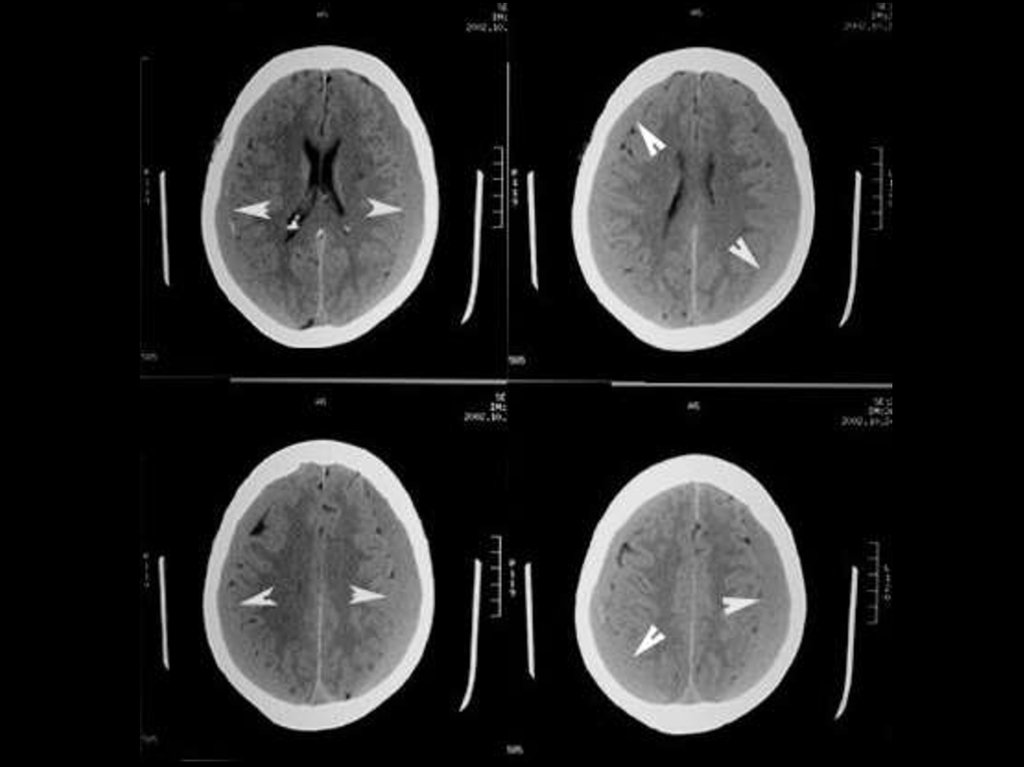

65-year-old man, history revealed 20 years of hypertension,

which was poorly controlled and smoking 1 to 2 packs of

cigarettes per day for last 35 years